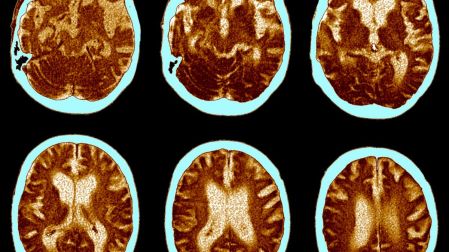

Los primeros síntomas de la demencia pueden tardar décadas en aparecer, pero los cambios cerebrales comienzan mucho antes. Investigadores han identificado un biomarcador en la sangre que podría advertir sobre el riesgo de deterioro cognitivo mucho antes de notar olvidos o confusiones.

El biomarcador identificado en el estudio se llama proteína tau fosforilada 217 (p-tau217). Esta proteína está relacionada con los cambios cerebrales que ocurren en la Enfermedad de Alzheimer, la causa más frecuente de demencia en el mundo.

En condiciones normales, la proteína tau ayuda a mantener la estructura interna de las neuronas, las células responsables de transmitir información en el cerebro. Sin embargo, cuando sufre alteraciones químicas anormales puede acumularse dentro de las neuronas y formar estructuras que interfieren con su funcionamiento.

Este proceso suele aparecer junto con la acumulación de placas de beta-amiloide, otro tipo de proteína que también se asocia con el Alzheimer. La combinación de ambos fenómenos provoca daño progresivo en las células nerviosas y afecta la memoria, el razonamiento y otras funciones mentales.

Durante ese periodo silencioso, el cerebro acumula proteínas anormales que dañan gradualmente las neuronas. Cuando aparecen los olvidos o problemas de memoria, el daño cerebral ya puede ser considerable.